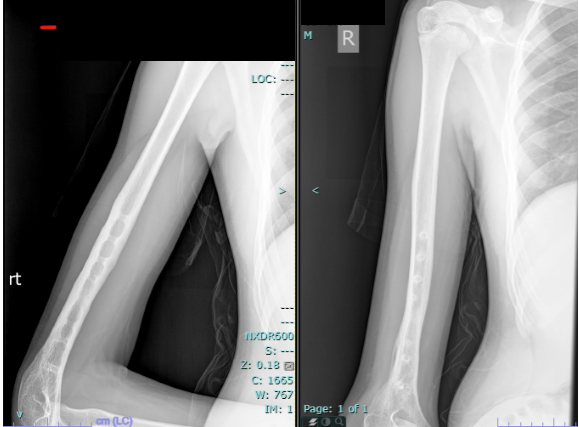

His wounds healed well, and there were no complications during the initial post-operative period. However, even after 7–8 months, radiographs showed no signs of union (Fig. 3 and 4).

Figure 3: Radiograph at 7 months showing non-union.

Figure 4: Radiograph at 8 months confirming non-union.